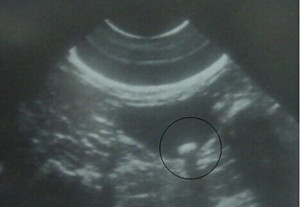

1.三维彩色B超(推荐): B超检查简便、经济、不开刀伤,可以发现2mm以上的输尿管结石(包括阴性结石),了解结石的位置和大小、集合系统的扩张程度、肾皮质厚度等,为治疗方法的选择提供参考,因此可以作为输尿管结石的常规检查方法。由于腹腔脏器的干扰,B超诊断输尿管中下段结石或较小的上段结石敏感性较低,此时需结合病史或其他检查方法以明确诊断。